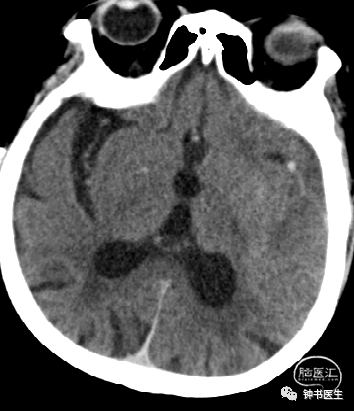

2017-7-6 CT

2017-7-7 CT

2017-7-12 CT